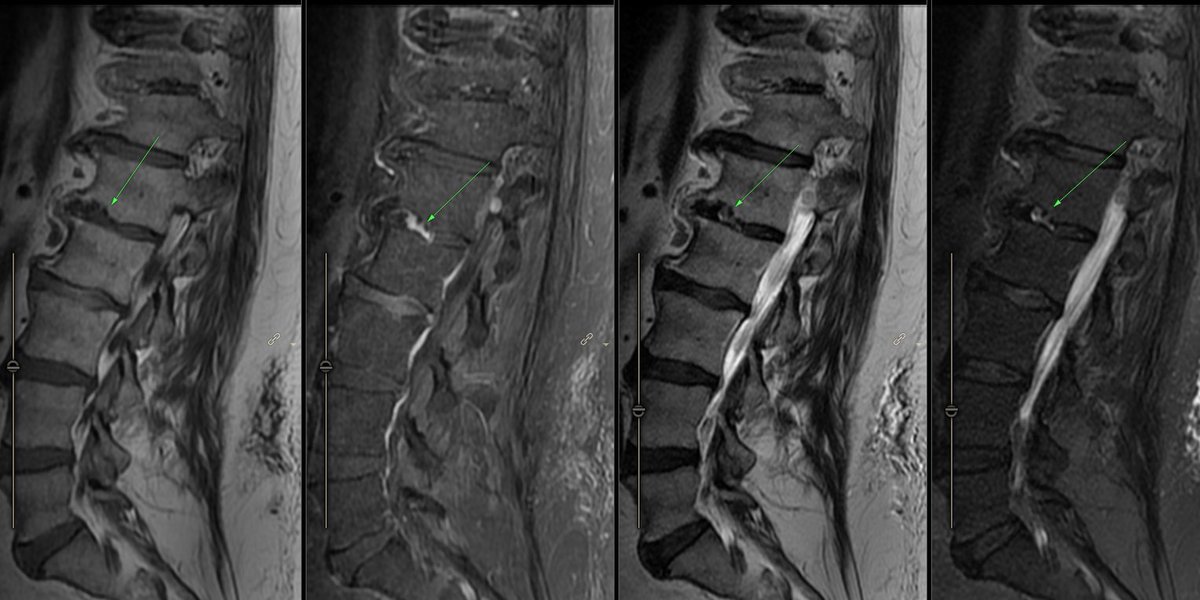

Enhancing Schmorl's node without end plate edema L1-L2( incidental schwannoma at same level). Would the spine folks call it acute schmorl's node? Invoke infection? #neurorad #spinerad #radres

gmoonis's tweet image. Enhancing Schmorl's node without end plate edema  L1-L2( incidental schwannoma at same level). Would the spine folks call it acute schmorl's node? Invoke infection?  #neurorad #spinerad #radres